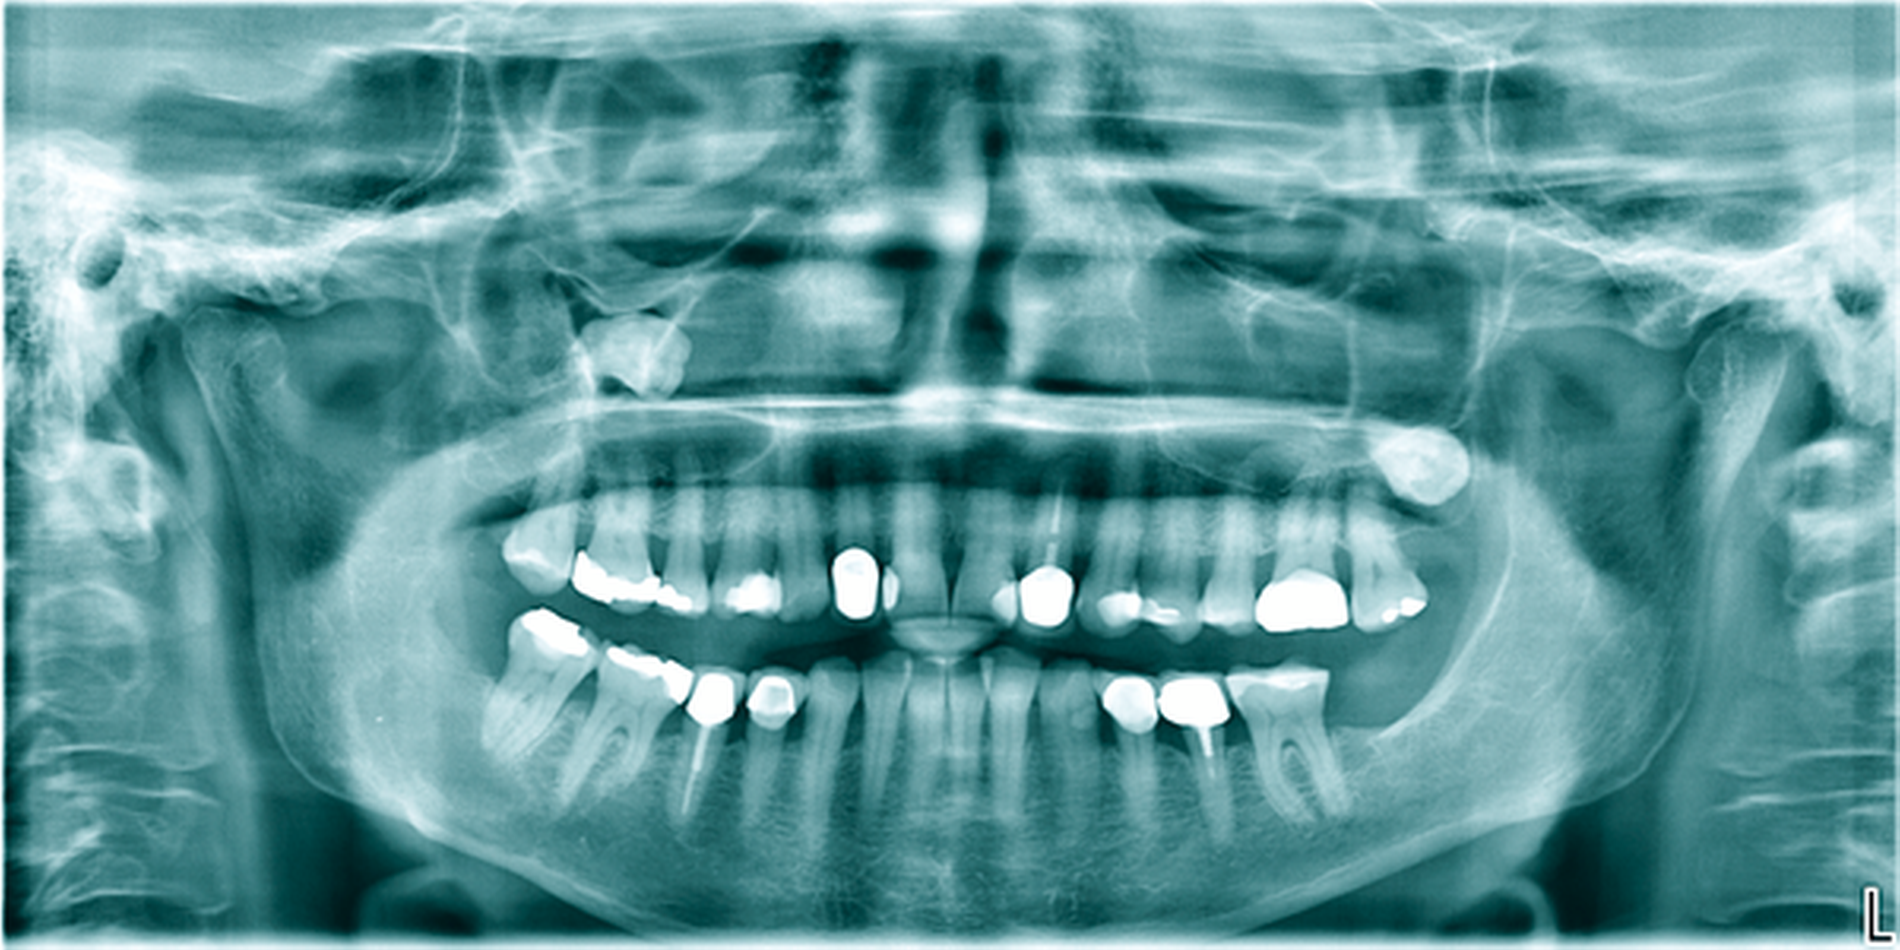

Ein 14-jähriger Patient wurde mit dem Zufallsbefund einer zystischen Raumforderung im Bereich des Kieferwinkels rechts in unser MVZ überwiesen (Abbildung 5a). Aufgrund der Ausdehnung mit Affektion des N. alveolaris inferior sowie der Wurzelspitzen der Zähne 47 und 46 wurde sich nach Abwägung der perioperativen Risiken in enger Absprache mit den Eltern und dem Patienten gegen eine primäre Zystektomie mit Entfernung des extrem verlagerten Zahnes 48 entschieden. Eltern und Patient bevorzugten – trotz absehbar längerer Behandlungszeit – die primäre Verkleinerung der Zyste mittels Obturatortherapie.

Das histopathologische Gutachten ergab die Diagnose einer Keratozyste. Daher erfolgte bereits nach drei Monaten eine Verlaufskontrolle mittels OPG, um ein Ansprechen auf die Therapie sicherzustellen. Nach sechs Monaten bereits war die Ausdehnung der Keratozyste so weit regredient, dass die vollständige Entfernung des Restbefunds sowie des Zahnes 48 mit risikoarmem Anfrischen des umliegenden Knochens in ambulanter ITN erfolgen konnte (Abbildung 5b). Die Zähne 18, 28 und 38 wurden dabei ebenfalls entfernt. Die Sensibilität der Unterlippe sowie der Zähne 46 und 47 konnte erhalten werden. Die Verlaufskontrolle nach einem weiteren halben Jahr zeigte eine gute knöcherne Durchbauung des ehemaligen Defekts im Bereich des Kieferwinkels rechts und der Patient blieb weiterhin beschwerdefrei (Abbildung 5c).